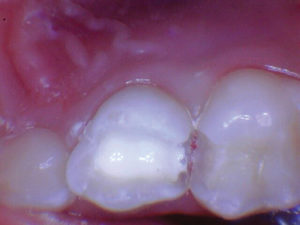

Caso 5

Una adolescente de 13 años presentada para un nuevo examen de paciente. Se observó una gran lesión cariosa en el primer molar permanente superior izquierdo, que presentaba síntomas de pulpitis reversible. Las opciones de tratamiento se discutieron con la paciente y su madre. Mis objetivos personales para este caso eran evitar la exposición de la pulpa y restaurar la forma y la función.

Figura 1. Presentación

clínica inicial del primer molar permanente superior izquierdo con caries

oclusal. |

Figura 2. Cuando la lesión

estaba sin techar, era evidente que había una lesión amplia y profunda. |